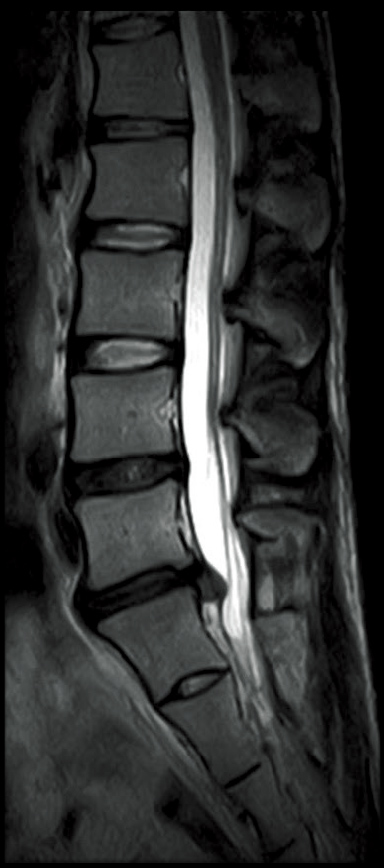

T2WI